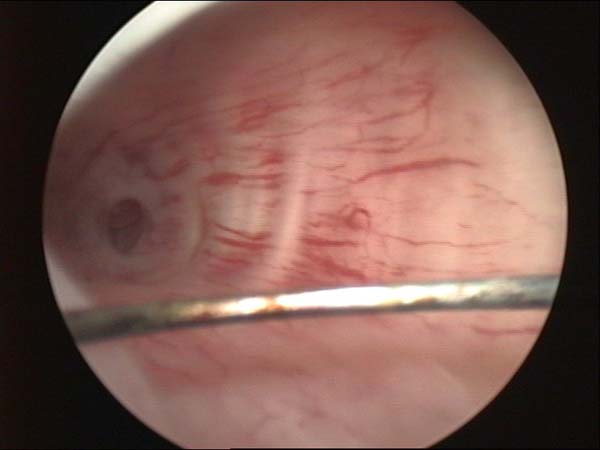

- Hysteroscopy Photos

Hysteroscopy Pictures | Dr N Layyous